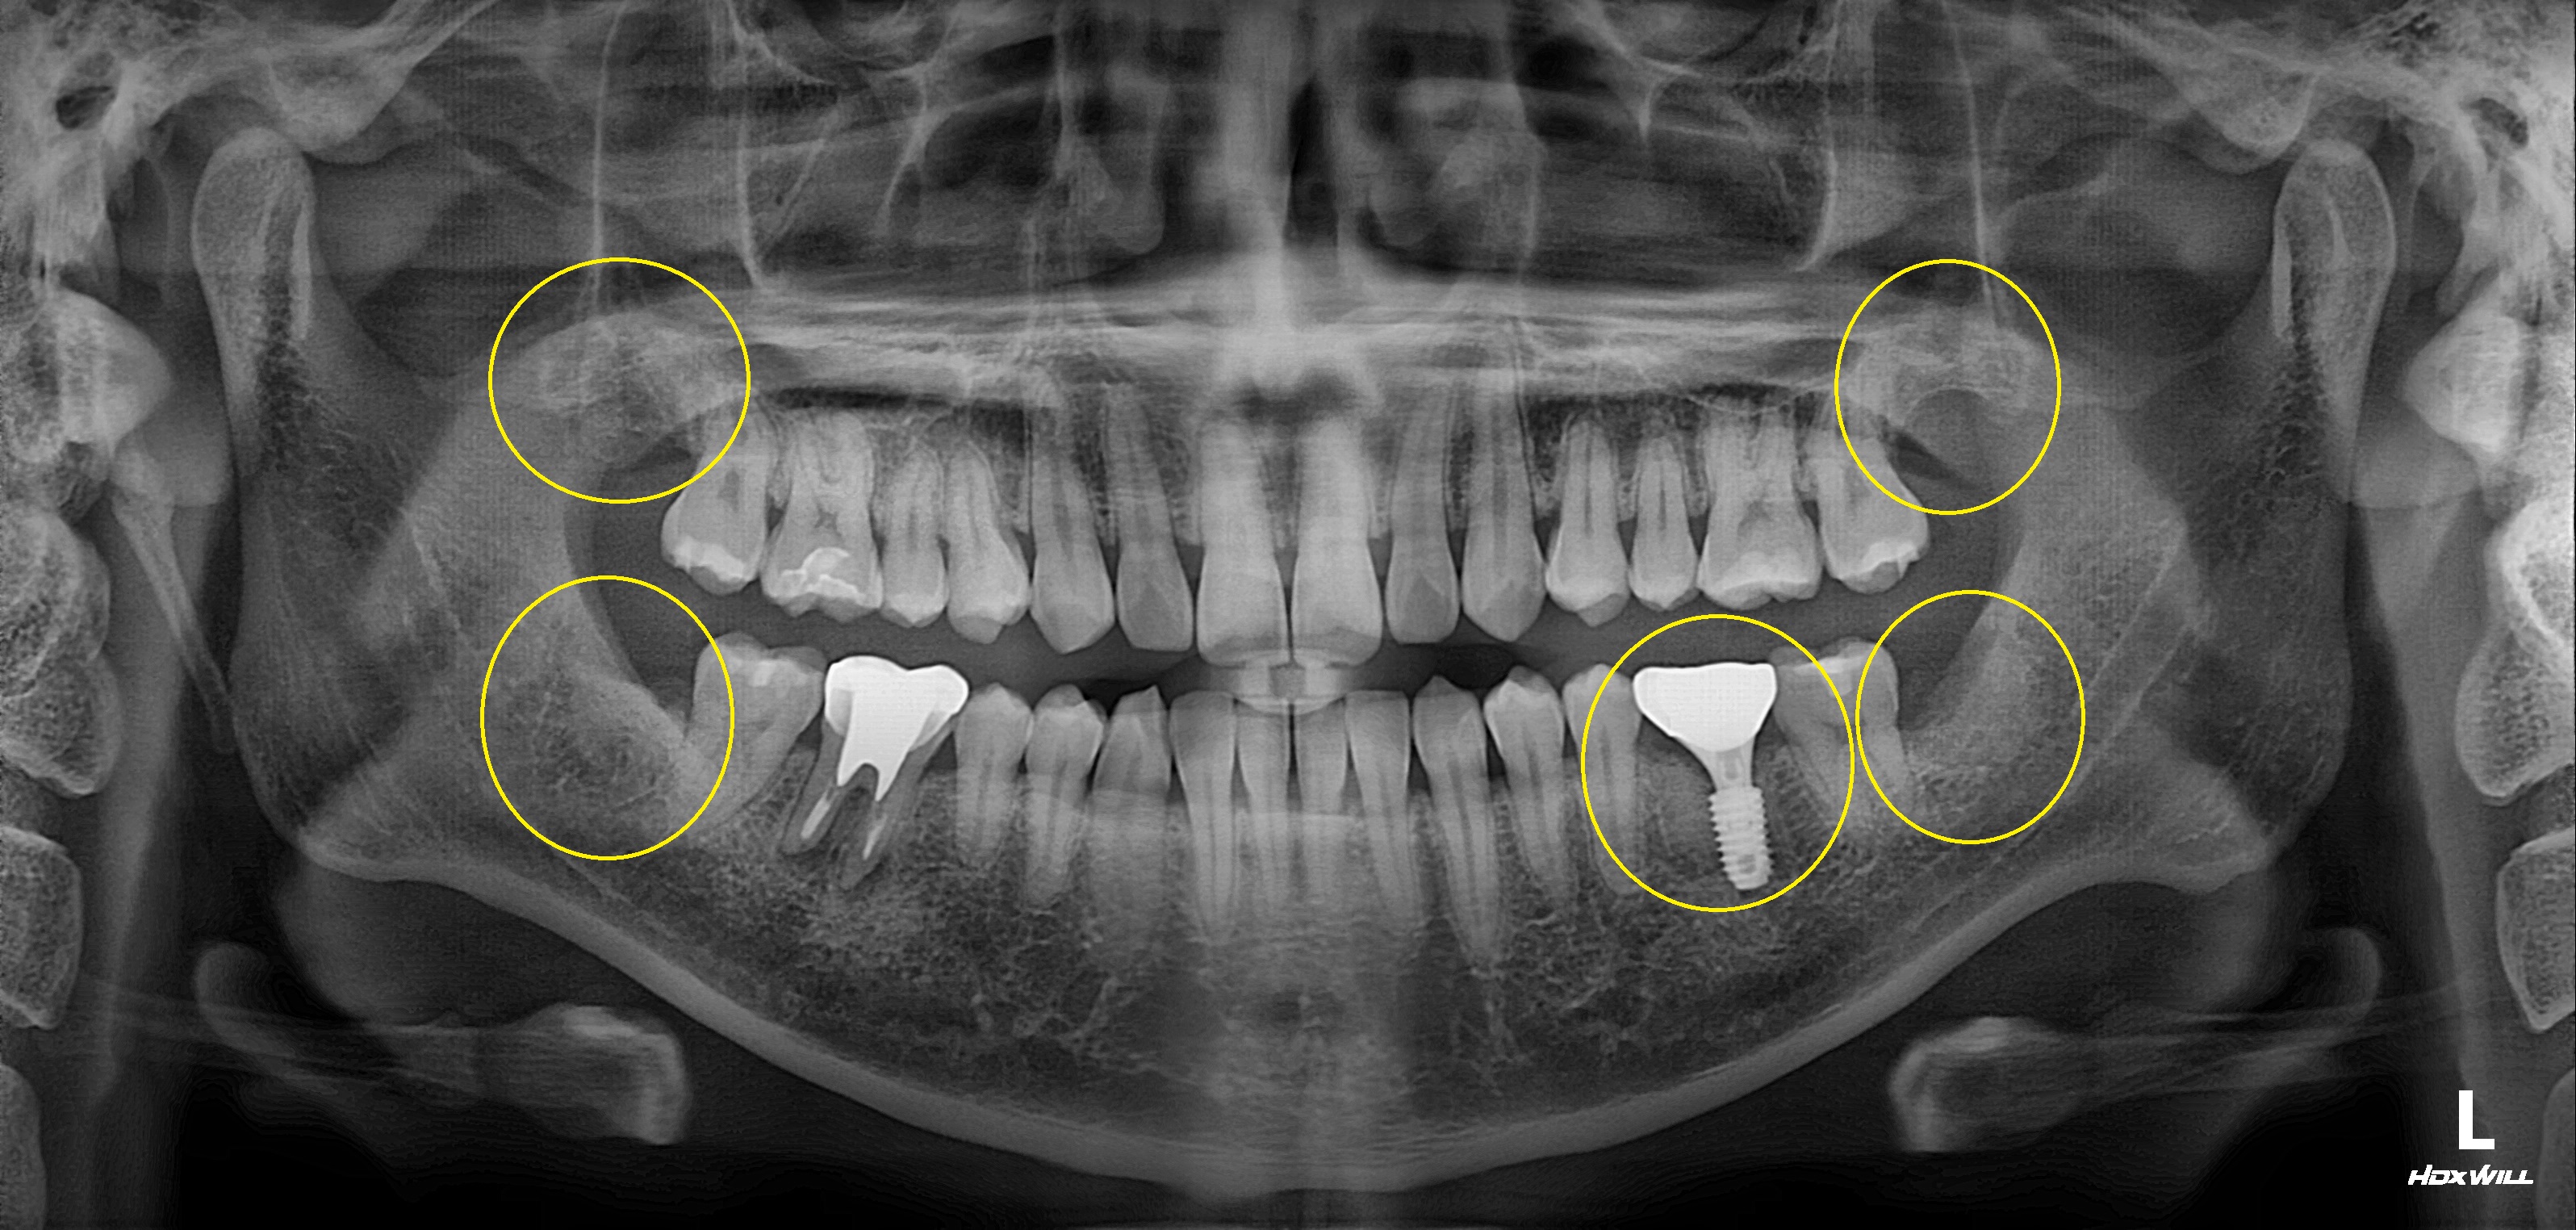

수술 전

수술 후

구치부 임플란트 식립사례

전후사진